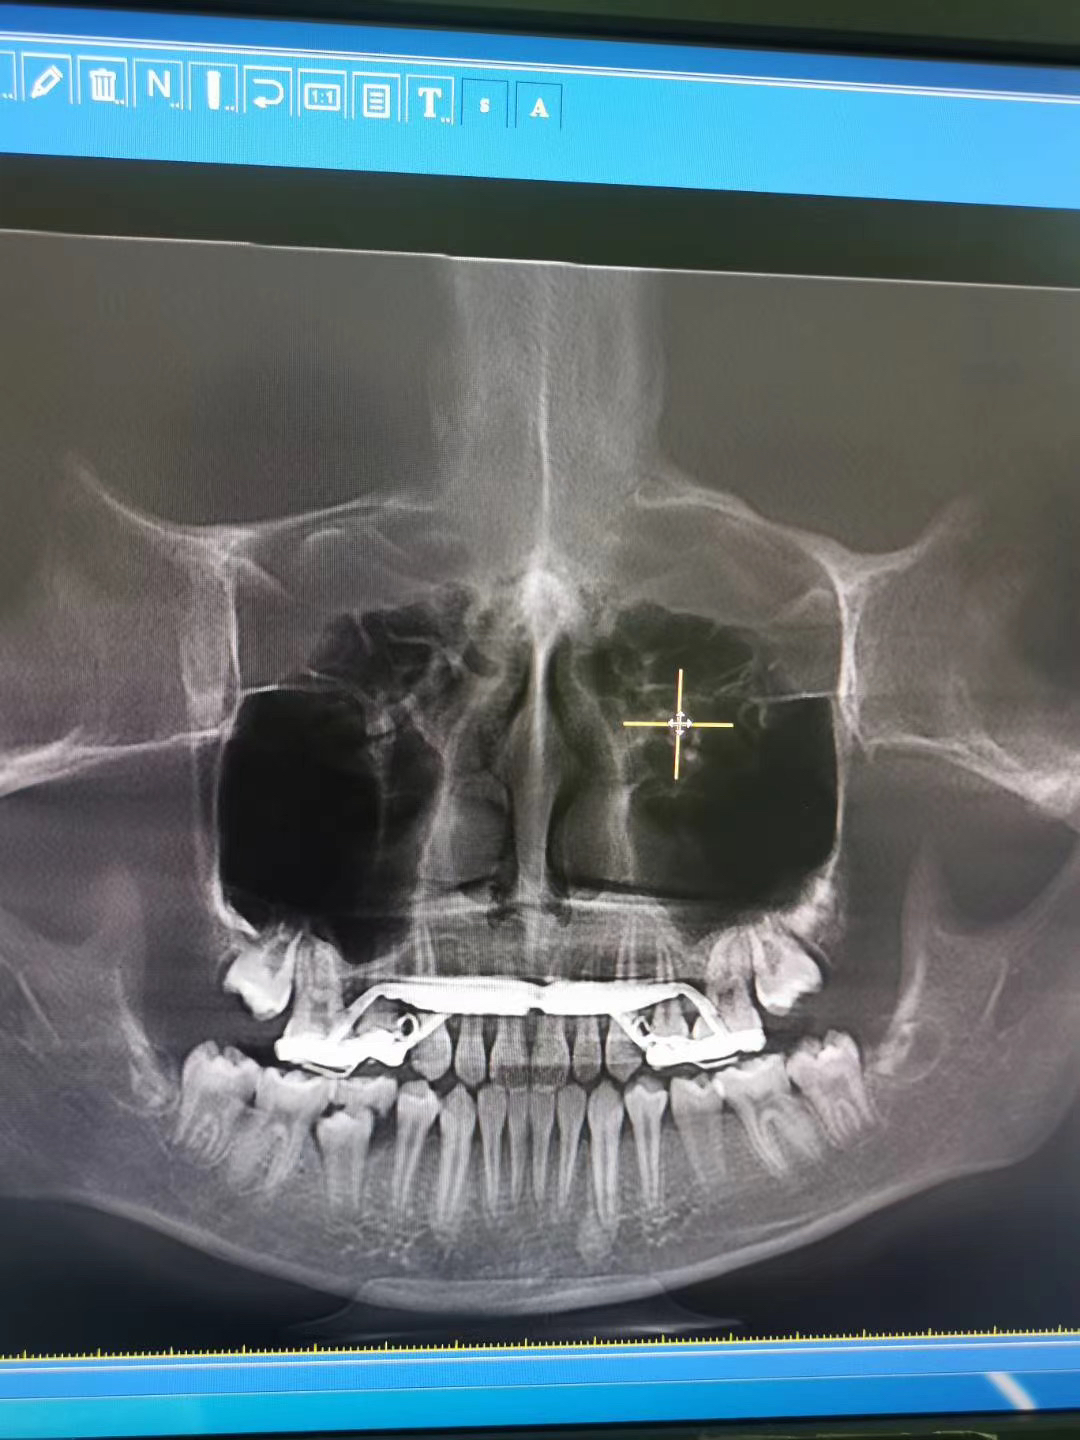

小朋友是替牙期,骨性地包天,做了一年多的前牵引,现在达到目标了。

图片发自160医生App